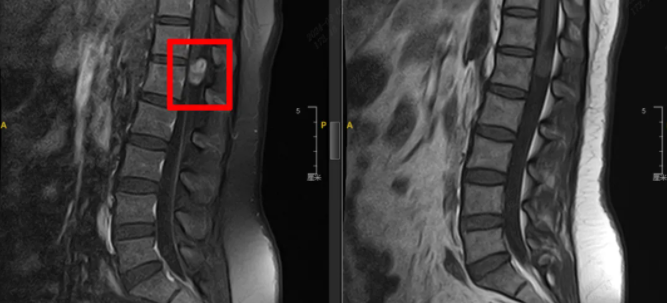

“手术指征明显,需尽快进行手术!”接诊的脊柱外科主任尚军对王女士的病史及相关检查进行了详细询问和查看后,诊断她为T12-L1椎体后缘髓外硬膜下占位,考虑神经鞘瘤可能性大。因占位效应明显,已严重压迫周围神经。若不及时解除压迫,神经根长期缺血,可能导致疼痛进行性加重,双侧肢体无力,甚至不同程度的瘫痪,严重时还会出现大小便功能障碍。

术中手术团队取出棘突椎板复合体,纵行切开硬脊膜,在3D显微镜下将病损与被包裹在一起的血管和脊髓神经精细剥离,尽可能减少脊髓神经的损害。成功剥离后,严密缝合硬脊膜,将棘突椎板复合体复位并固定,保证椎管的完整性、稳定性,防止术后椎管狭窄压迫脊髓,手术顺利完成!